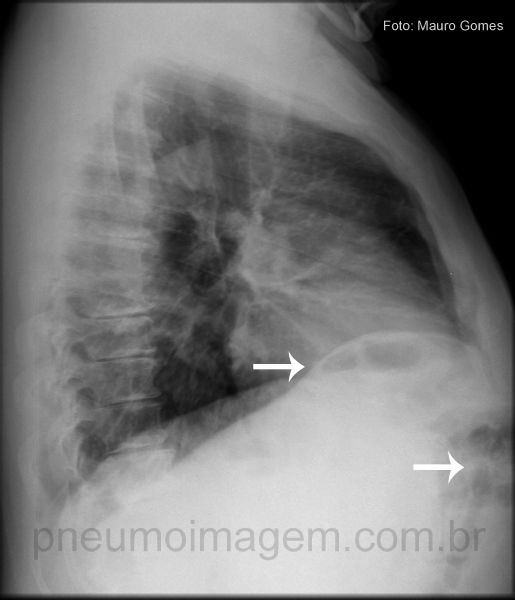

Sinal de Chilaiditi é um termo radiográfico usado quando o cólon (seta branca), intestino delgado ou estômago é visto interposto entre o fígado e o diafragma direito.

A radiografia de tórax mostra a presença das alças do cólon com gás abaixo do diafragma direito. Geralmente é assintomático e se constitui em achado radiológico (0,025% dos exames).

Cólon interposto abaixo do diafragma e anteriormente (setas).

Quando esta alteração está associada a dor, náuseas, vômitos, distensão abdominal ou mesmo volvo de cólon sigmóide, pode ser causa rara de abdome agudo obstrutivo e ser chamada por Síndrome de Chilaiditi. Chaves: colon (white).